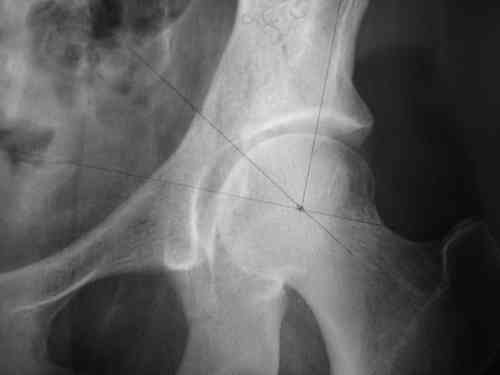

Спасибо за клинические примеры и комментарии. Если честно то просто восхищен представлеными R-ммами (классно сделали!!!). По поводу обсуждаемого больного: конечно КТ и дополнительные R-ммы сделаем. Но хочу напомнить, что после травмы прошло более 6 лет, на сегодняшний день клинически еще и R-ки признаки нестабильности эндопротеза( как бедренного компонента так и чашки). Хочется определиться как делать в аппарате или одномоментно открыто. Лично я склоняюсь к аппаратному лечению на первом этапе.

прилагаю пример с такой же давностью травмы, репонировали аппаратом

задача непростая, если мало опыта в этом деле, подумайте еще раз